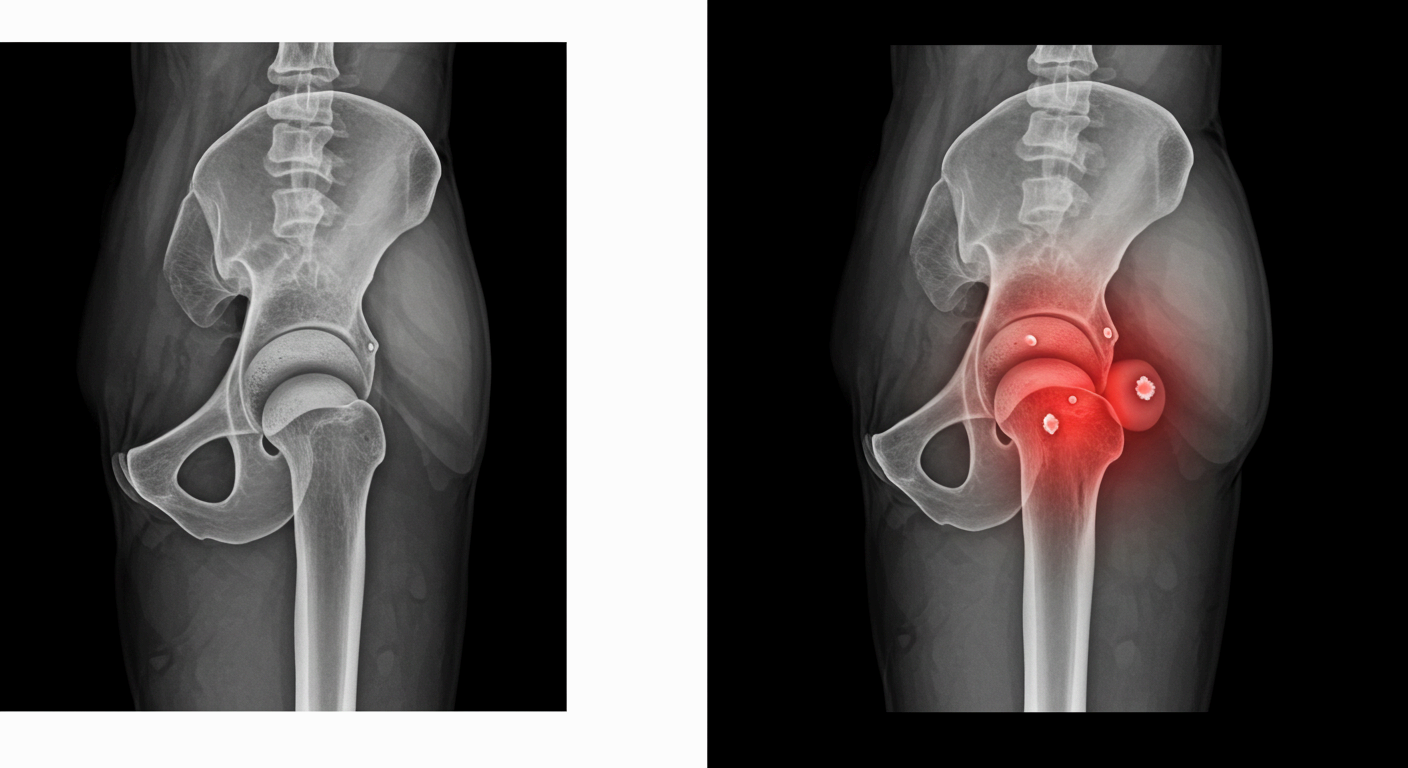

고관절 통증은 단순히 엉덩이 부위만 아픈 것이 아니라, 사타구니·허벅지·엉덩이·무릎 등 여러 부위로 연관 통증이 나타나는 복합 증상입니다.

고관절 통증의 대표적인 증상들

- 사타구니 안쪽이 뻐근하고 찌릿한 느낌

- 걸을 때마다 사타구니 안쪽이 당기고, 앉았다 일어날 때 통증이 심해짐

- 특히 고관절 충돌 증후군이나 점액낭염에서 자주 나타나는 증상

증상이 나타나는 위치별 주요 질환

| 사타구니 안쪽 | 고관절 충돌 증후군, 대퇴골두 괴사 |

| 허벅지 앞쪽 | 점액낭염, 고관절 활액막염 |

| 엉덩이 바깥쪽 | 장경인대증후군, 둔부근막통증증후군 |

| 무릎까지 저림 | 좌골신경 압박, 골반 불균형 |

| 움직일 때 ‘딱’ 소리 | 고관절 스냅 증후군 |